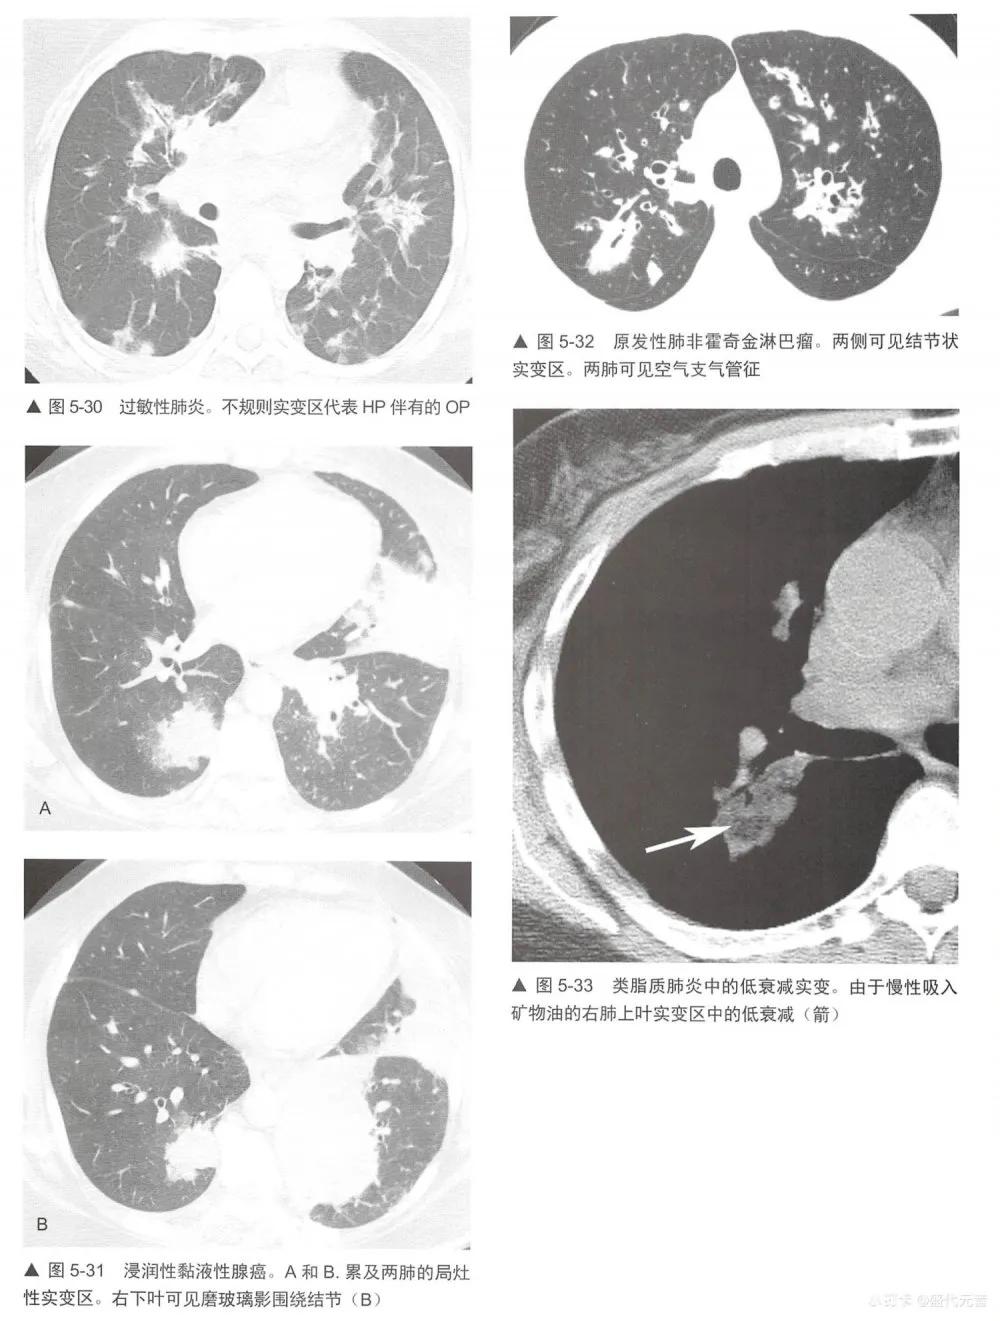

在定义上,实变是肺泡内空气为液体、细胞、组织或其他物质取代。大部分有气腔充盈,但有些可形成广泛、融合性间质异常的病变,如NSIP或结节病,也能导致实变在伴有其他异常为著,如小结节的实变病例中,要以其他为著的异常作鉴别诊断。在这些病例中,实变可能代表融合的病变。

实变的鉴别诊断与磨玻璃影(表5-1)有相当大的重叠,事实上,许多表5-1列出的疾病都显示为这两种表现的混合(表5-5)。实变的鉴别诊断包括不同原因的肺炎:最典型的是细菌性(图5-28),但也包括分枝杆菌、真菌性肺炎(图5-29)、支原体、耶氏孢子菌和病毒性肺炎; 0P (图5-24和图5-25);嗜酸性肺炎(图5-26,图5-27),如NSIP和DIP的间质性肺炎;HP (图5-30);放射性肺炎、浸润性黏液腺癌(图5-16和图5-31); LIP;淋巴瘤(图5-32)和淋巴增生性疾病;肺泡蛋白沉着症;结节病;药物反应,肺水肿和肺出血;AIP, DAD和ARDS。与吸入动、植物油脂或矿物油有关的外源性类脂性肺炎,可导致磨玻璃影或实变,此时因含有脂肪是低衰减的(图5-33)。